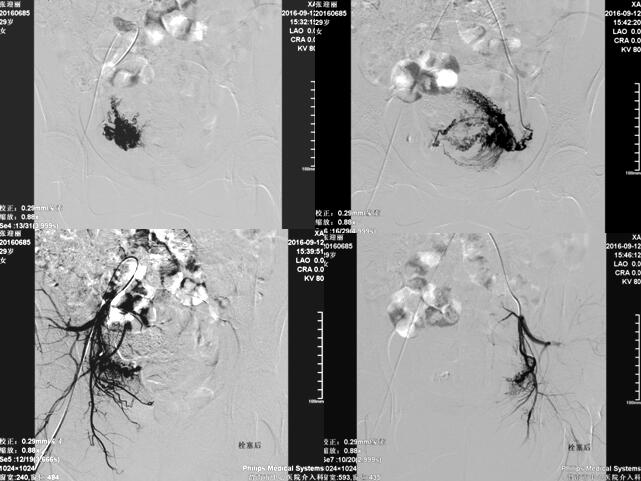

乐鱼在线登录入口介入科在李建国主任带领下自2006年开展子宫肌瘤栓塞术,现已完成数百例相关疾病介入治疗,为渭南地区及各县患者提供了全新的子宫肌瘤治疗方法,避免患者子宫全切。子宫肌瘤栓塞术是一种安全有效的治疗方法,是由介入医生经病人腹股沟股动脉导入一导管至肌瘤的血供(子宫动脉)处,释放一些细微颗粒,弹簧圈、或者球囊等阻断肌瘤的血供、供养及出血部位,使肌瘤纤维化,出血停止,肌瘤萎缩。所有经过介入治疗的患者术后大约3-6个月相关症状完全消失。

经子宫动脉栓塞术还可应用于子宫腺肌症、胎盘植入、瘢痕妊娠、前置胎盘及产后大出血等疾病,以下为一例产后大出血患者介入治疗图片: